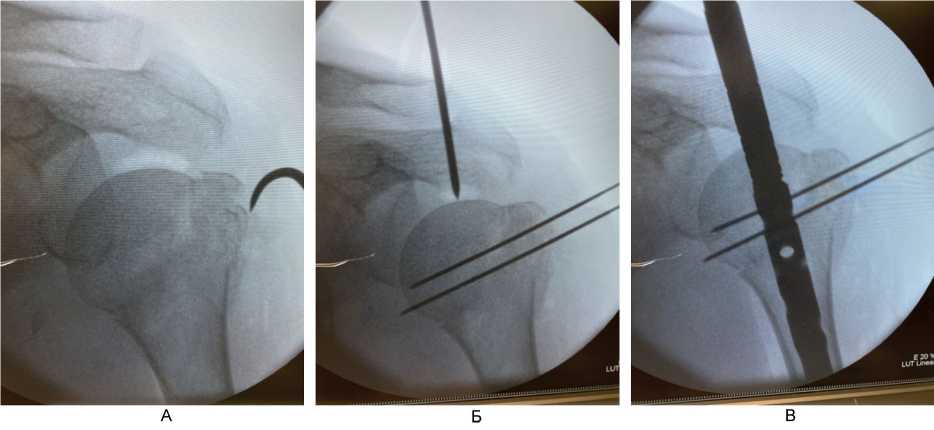

При переломах типа А и В по АО с 2020 г. по настоящее время использовали методику интрамедуллярного остеосинтеза из доступов по типу проколов (до 1 см) с применением непрямой репозиции с помощью спиц-джойстиков (рис. 4), время опреации – 31 мин.

Рис. 4. Непрямая репозиция под рентгенологическим контролем (ЭОП) с помощью спиц-джойстиков при переломах типа А и В по АО. А – установка толстой спицы-джойстика в проксимальный отломок; Б – репозиция варусного отклонения проксимального отломка; В – выбор точки для вскрытия интрамедуллярного канала плечевой кости под имплантат; Г – контроль положения направителя для вскрытия интрамедуллярного канала плечевой кости